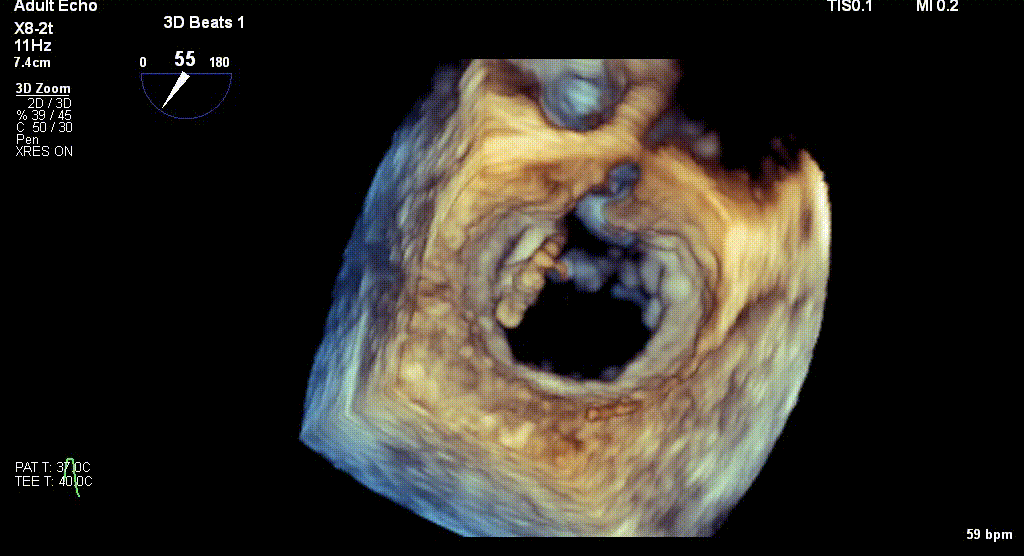

术前TEE评估

原发性MR,交界C1区脱垂,反流程度4+;二尖瓣瓣口面积3.88cm²,平均跨瓣压差2mmHg;二尖瓣前叶(A1)长度16.2mm,二尖瓣后叶长度(P1)长度9.9mm,脱垂高度6mm。